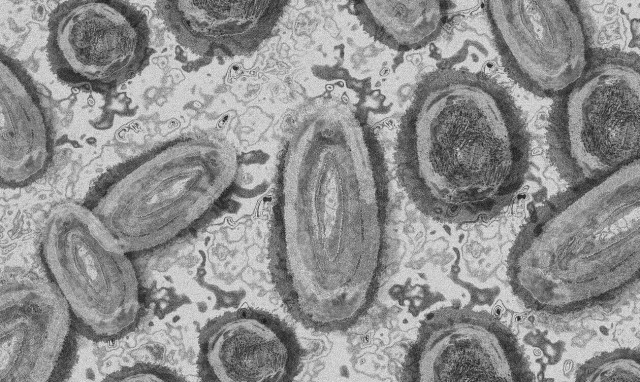

ΕΥΛΟΓΙΑ ΤΩΝ ΠΙΘΗΚΩΝ

Λιθουανία: Πρώτο επιβεβαιωμένο κρούσμα ευλογιάς των πιθήκων στη χώρα